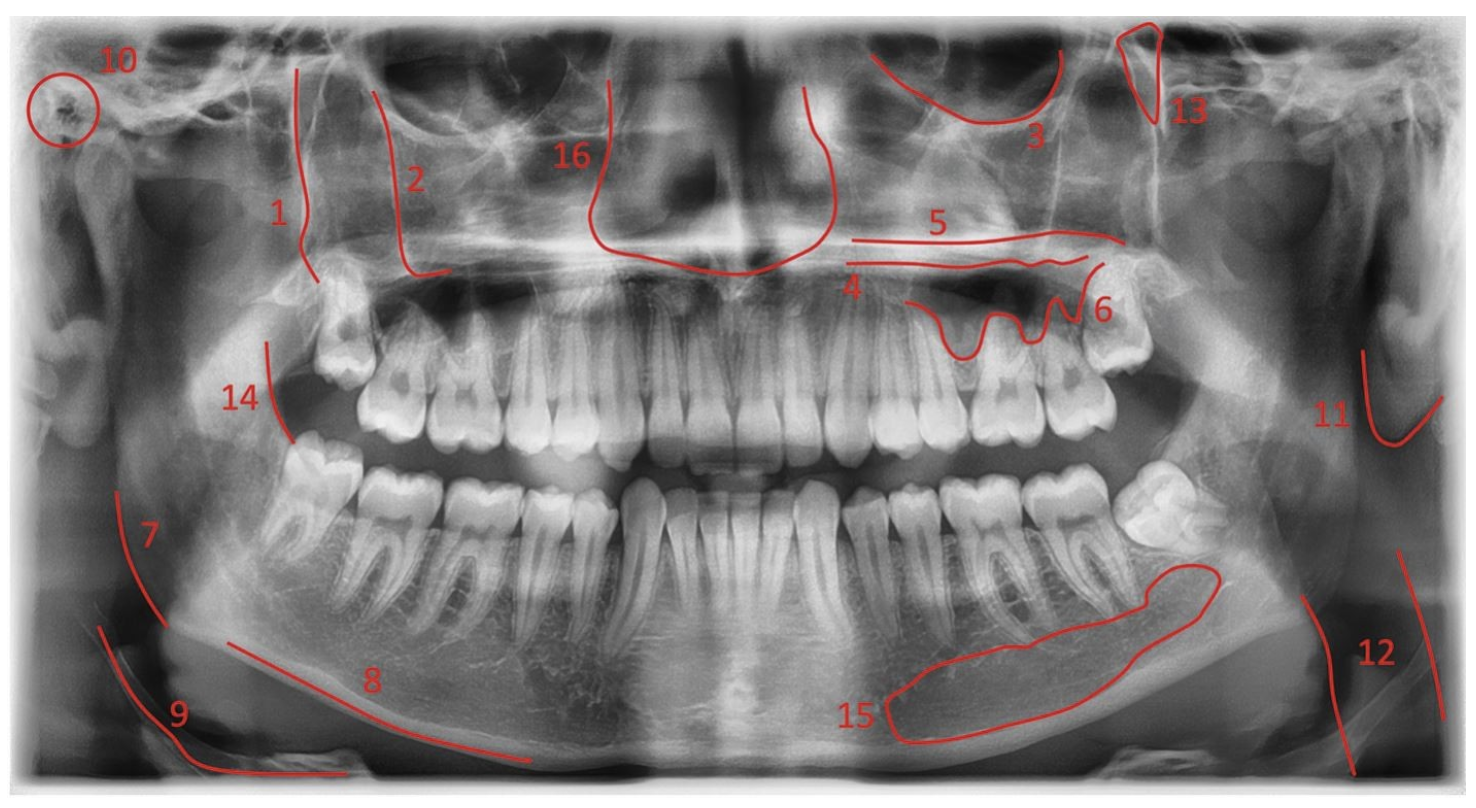

In OPG imaging, AI is applied at the screening and visualization level.

Here’s how it works in practice:

This allows:

You (as a dentist) to quickly identify areas that need attention

Faster initial case understanding before detailed review

But importantly: These markings are indicative, not diagnostic

They act as a visual aid, helping you focus not replacing your evaluation.